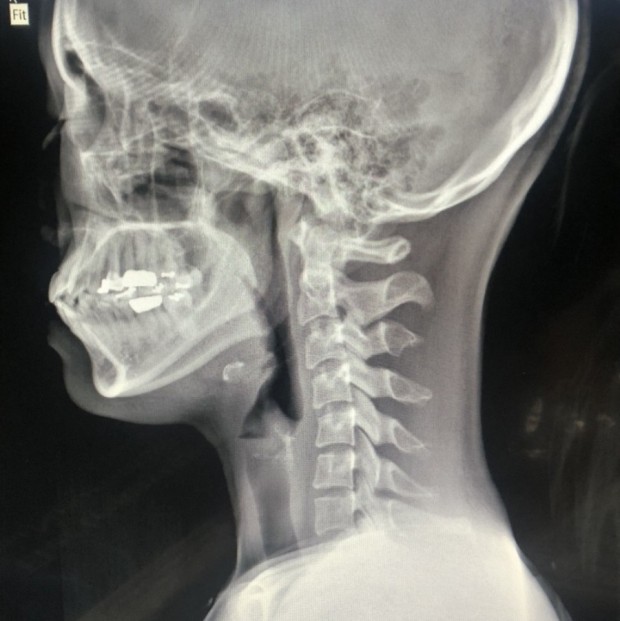

목디스크 증상 목디스크란 목 뼈 사이의 디스크가 원래의 자리에서 이탈하면서 신경을 누르거나 뼈조직이 비정상적으로 자라나 목을 지나가는 척추신경을 누르게 됨으로써 통증을 느끼는 질환입니다. 예전에는 40대 이상의 분들한테서 주로 나타나는 질환이었지만 요즘은 젊은 세대에도 흔하게 볼 수 있는 질환이 되었습니다.

외부로부터 강력한 충격은 주로 교통사고로 인해서 발생돼요. 교통사고만 나면 주로 목을 잡게 되죠? 뒤차에 받혔을 때 주로 경추에 충격을 주어 주로 경추염좌 진단을 받는데 가벼운 증상일 때 빨리 치료를 해야 되므로 입원해서 치료를 받는 게 좋다. 퇴형성으로 목 디스크 증상이 조금씩은 다 있는데 이럴 때 교통사고 나면 전문기관 가서 X-Ray 촬영하다 보면 디스크(경주 염좌) 진단을 받게 됩니다.

우리의 성인 기준 머리 무게는 약 5.5kg 정도이죠. 목을 앞으로 숙이는 잘못된 자세를 오랫동안 지속하다 보면 목 디스크 증상 발생의 원인이 돼요. 스마트폰의 장시간 사용하기 그리해서 많이 발생되고 또한 직업병으로 컴퓨터를 오래동안 사용하기 그리해서 목뼈의 C자형이 변해서 거북목처럼 변형되기도 합니다..